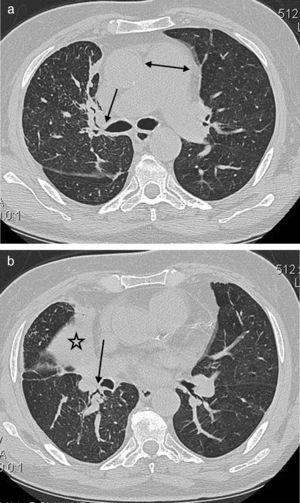

Un varón de 64 años de edad con tos y disnea. a) Imagen de TC a nivel del tronco de la arteria pulmonar que muestra un engrosamiento de tejido blando peribronquial central (flecha) y estenosis del bronquio del LSD. Se observa también el agrandamiento del tronco de la arteria pulmonar (doble punta de flecha). b) TC de tórax con ventana temporal que muestra el colapso del LMD (estrella), así como un engrosamiento del tejido blando peribronquial del LID (flecha) con obliteración del bronquio del segmento apical del lóbulo inferior derecho.

Se observó un engrosamiento de tejido blando peribronquial central (fig. 2) en 37 (63,8%) casos. Ello afectaba predominantemente al lado derecho (lóbulo superior derecho [LSD], n=14; lóbulo superior izquierdo [LSI], n=9; lóbulo medio derecho [LMD], n=23; língula, n=7; lóbulo inferior derecho [LID], n=19; lóbulo inferior izquierdo [LII], n=10). El manguito de infiltración peribronquial intraparenquimatoso (fig. 3 a) se observó en 36 (62%) pacientes, con una mayor tendencia a afectar al lado derecho (LSD, n=12; LSI, n=11; LMD, n=24; língula, n=14; LID, n=27; LII, n=18). El engrosamiento de tejido blando peribronquial central y el manguito de infiltración peribronquial intraparenquimatoso fueron más frecuentes en los bronquios del LMD y LID, respectivamente.

La estenosis y la obstrucción se observaron en 37 (63,8%) y en 11 (19%) pacientes, respectivamente. Se observaron estenosis bronquiales múltiples en 23 (39,7%) pacientes (2 bronquios, n=12; 3 bronquios, n=9; 5 bronquios, n=2). La estenosis bronquial fue más prevalente en los lóbulos derechos que en los contralaterales (LSD, n=16; LSI, n=6; LMD, n=21; língula, n=7; LID, n=14; LII, n=10).

De igual modo, la obstrucción bronquial se observó con mayor frecuencia en el lado derecho (LSD, n=3; LSI, n=1; LMD, n=7). No se detectó obstrucción bronquial en la língula, ni en los lóbulos inferiores derecho o izquierdo. Tiene interés señalar que el bronquio del LMD fue el más comúnmente afectado por la antracofibrosis, con estenosis u obstrucción.